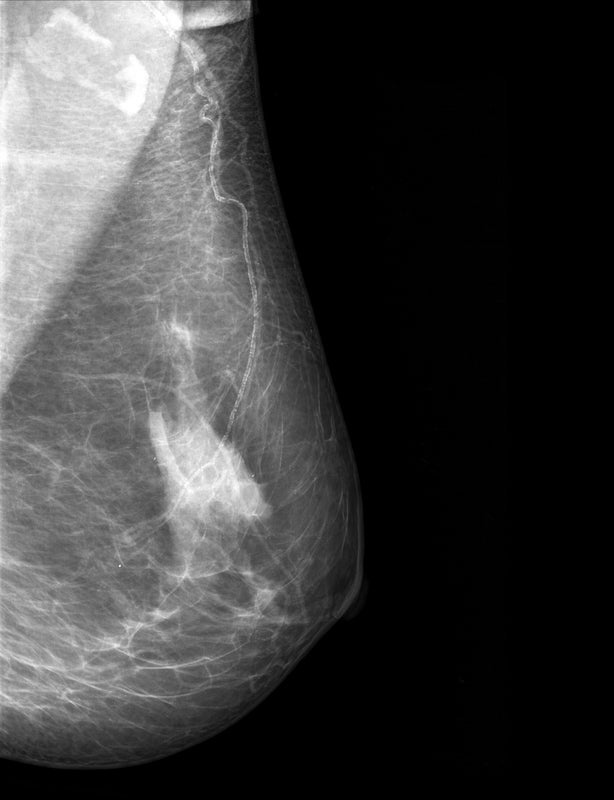

Die Studie prüfte die Leistung eines KI-basierten Ansatzes anhand von Mammographien von mehr als 100.000 Frauen in Deutschland, darunter mehr als 4.400 mit der Diagnose Brustkrebs. Die Sensitivität der Untersuchungsmethode konnte in einigen Fällen um bis zu 7,2 Prozentpunkte verbessert werden.

Der neue Ansatz kombiniert die Stärken von Radiologen und KI, indem die Mammographien von Fall zu Fall von der einen oder der anderen Partei befundet werden. Das bedeutet: Weil sie enorm schnell arbeitet, analysiert die KI zunächst alle Datensätze. Wenn die KI keine klare Entscheidung treffen kann, übergibt sie an die menschlichen Experten. Zusätzlich gibt es noch ein Sicherheitsnetz, das die Radiologen unterstützt. Es wird immer dann aktiv, wenn die Ergebnisse der KI nicht mit denen der Medizinern übereinstimmen. „Auf diese Weise können auch potenziell übersehene Karzinome entdeckt werden“, erklärt Prof. Dr. Lale Umutlu, stellvertretende Direktorin des Instituts für Diagnostische und Interventionelle Radiologie und Neuroradiologie am UK Essen.